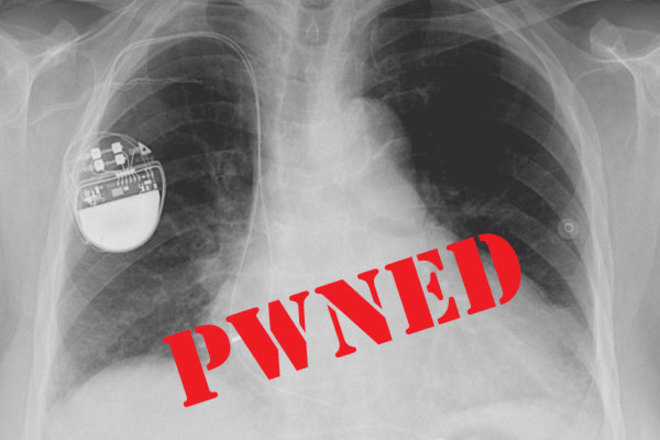

How to Hack Pacemakers, Insulin Pumps, & Even Tombstones